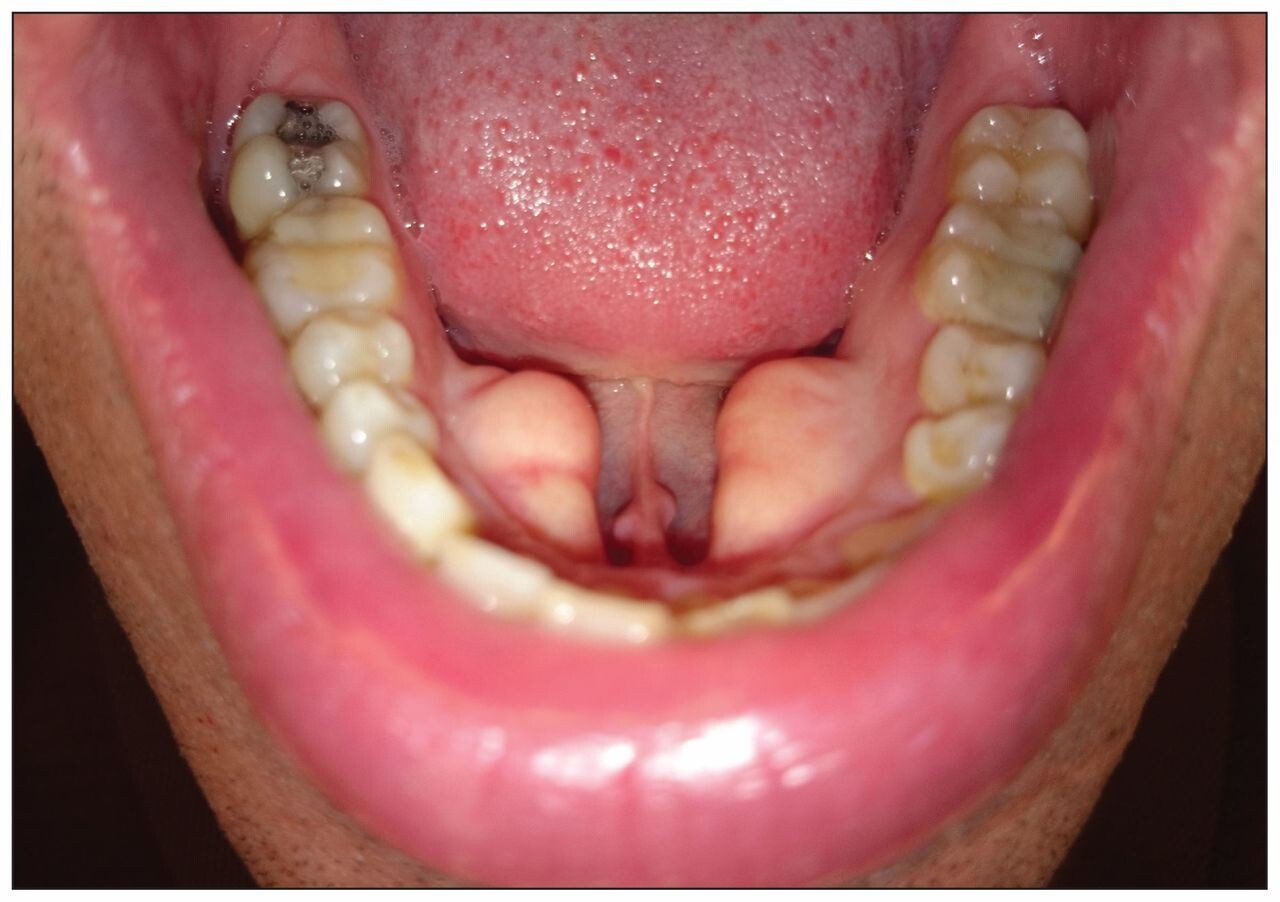

The type of exostosis you have depends on its location in your mouth. The most commonly occurring bone growths are found in the mouth's roof (torus palatinus) and beneath the tongue (torus mandibularus). Buccal exostoses are hard bony protrusions on the outside of your gums and are less common. Torus palatinus is often a singular growth, whereas torus mandibularus and buccal exostoses tend to be bilateral, meaning they happen on both sides of the mouth.

Exostoses are considered a variation of normal, and most often, they pose no health concern at all. Occasionally they can develop some adverse effects, especially if they become large enough to interfere with the functioning of your mouth. For instance, a torus mandibularus can make it difficult to speak properly if it grows to a certain size. Another potential issue is that the tissue covering bone growths is very thin and could get scratched or injured from sharp food, resulting in ulcer formation. Also, if you have missing teeth and are considering dentures, all types of exostosis can potentially interfere with the placement of your artificial teeth. Some people may want a growth removed due to aesthetic concerns.